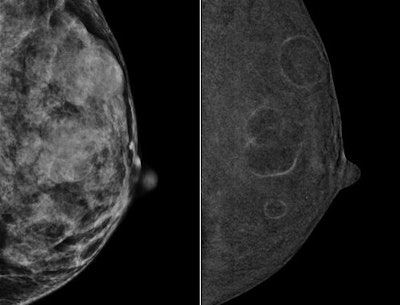

The findings are good news for a healthcare system burdened by inflated costs. Contrast mammography combines low-energy digital mammography images with contrast-enhanced subtracted images for better sensitivity and specificity than digital mammography alone.

But breast MRI is expensive, which makes contrast mammography an attractive alternative, especially because CEDM also produces images that offer information on a lesion's vascularity (AJR, April 5, 2017).